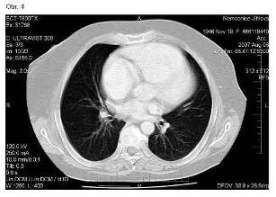

Pacientka zahájila chemoterapii režimem CDDP +

topotecan v květnu 2007. Po 4. cyklu v srpnu 2007 byla provedena

kontrolní CT vyšetření a bylo zjištěno úplné vymizení všech známek

nemoci jak v pánvi (obr. 3), tak na plicích (obr. 4).